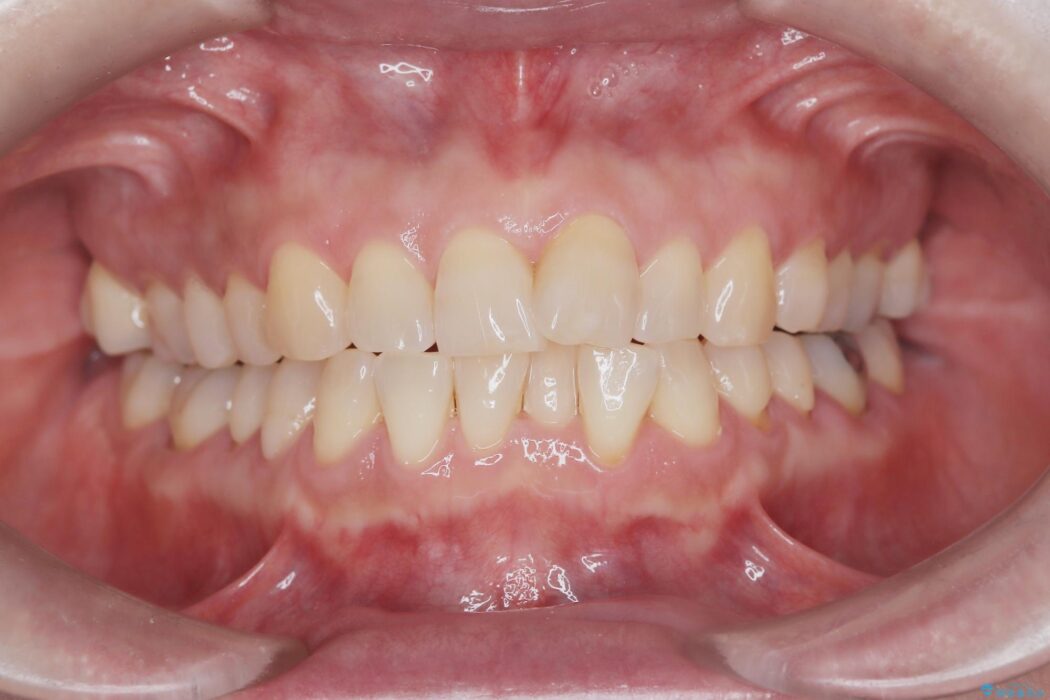

前歯のガタつきが気になるとご来院された患者様です。

ワイヤー矯正ならではの確実な歯のコントロールにより、当初の計画通り約1年という短い期間で、前歯のガタつきが解消。見た目が美しく整っただけでなく、清掃しやすい機能的な歯並びを獲得していただけました。